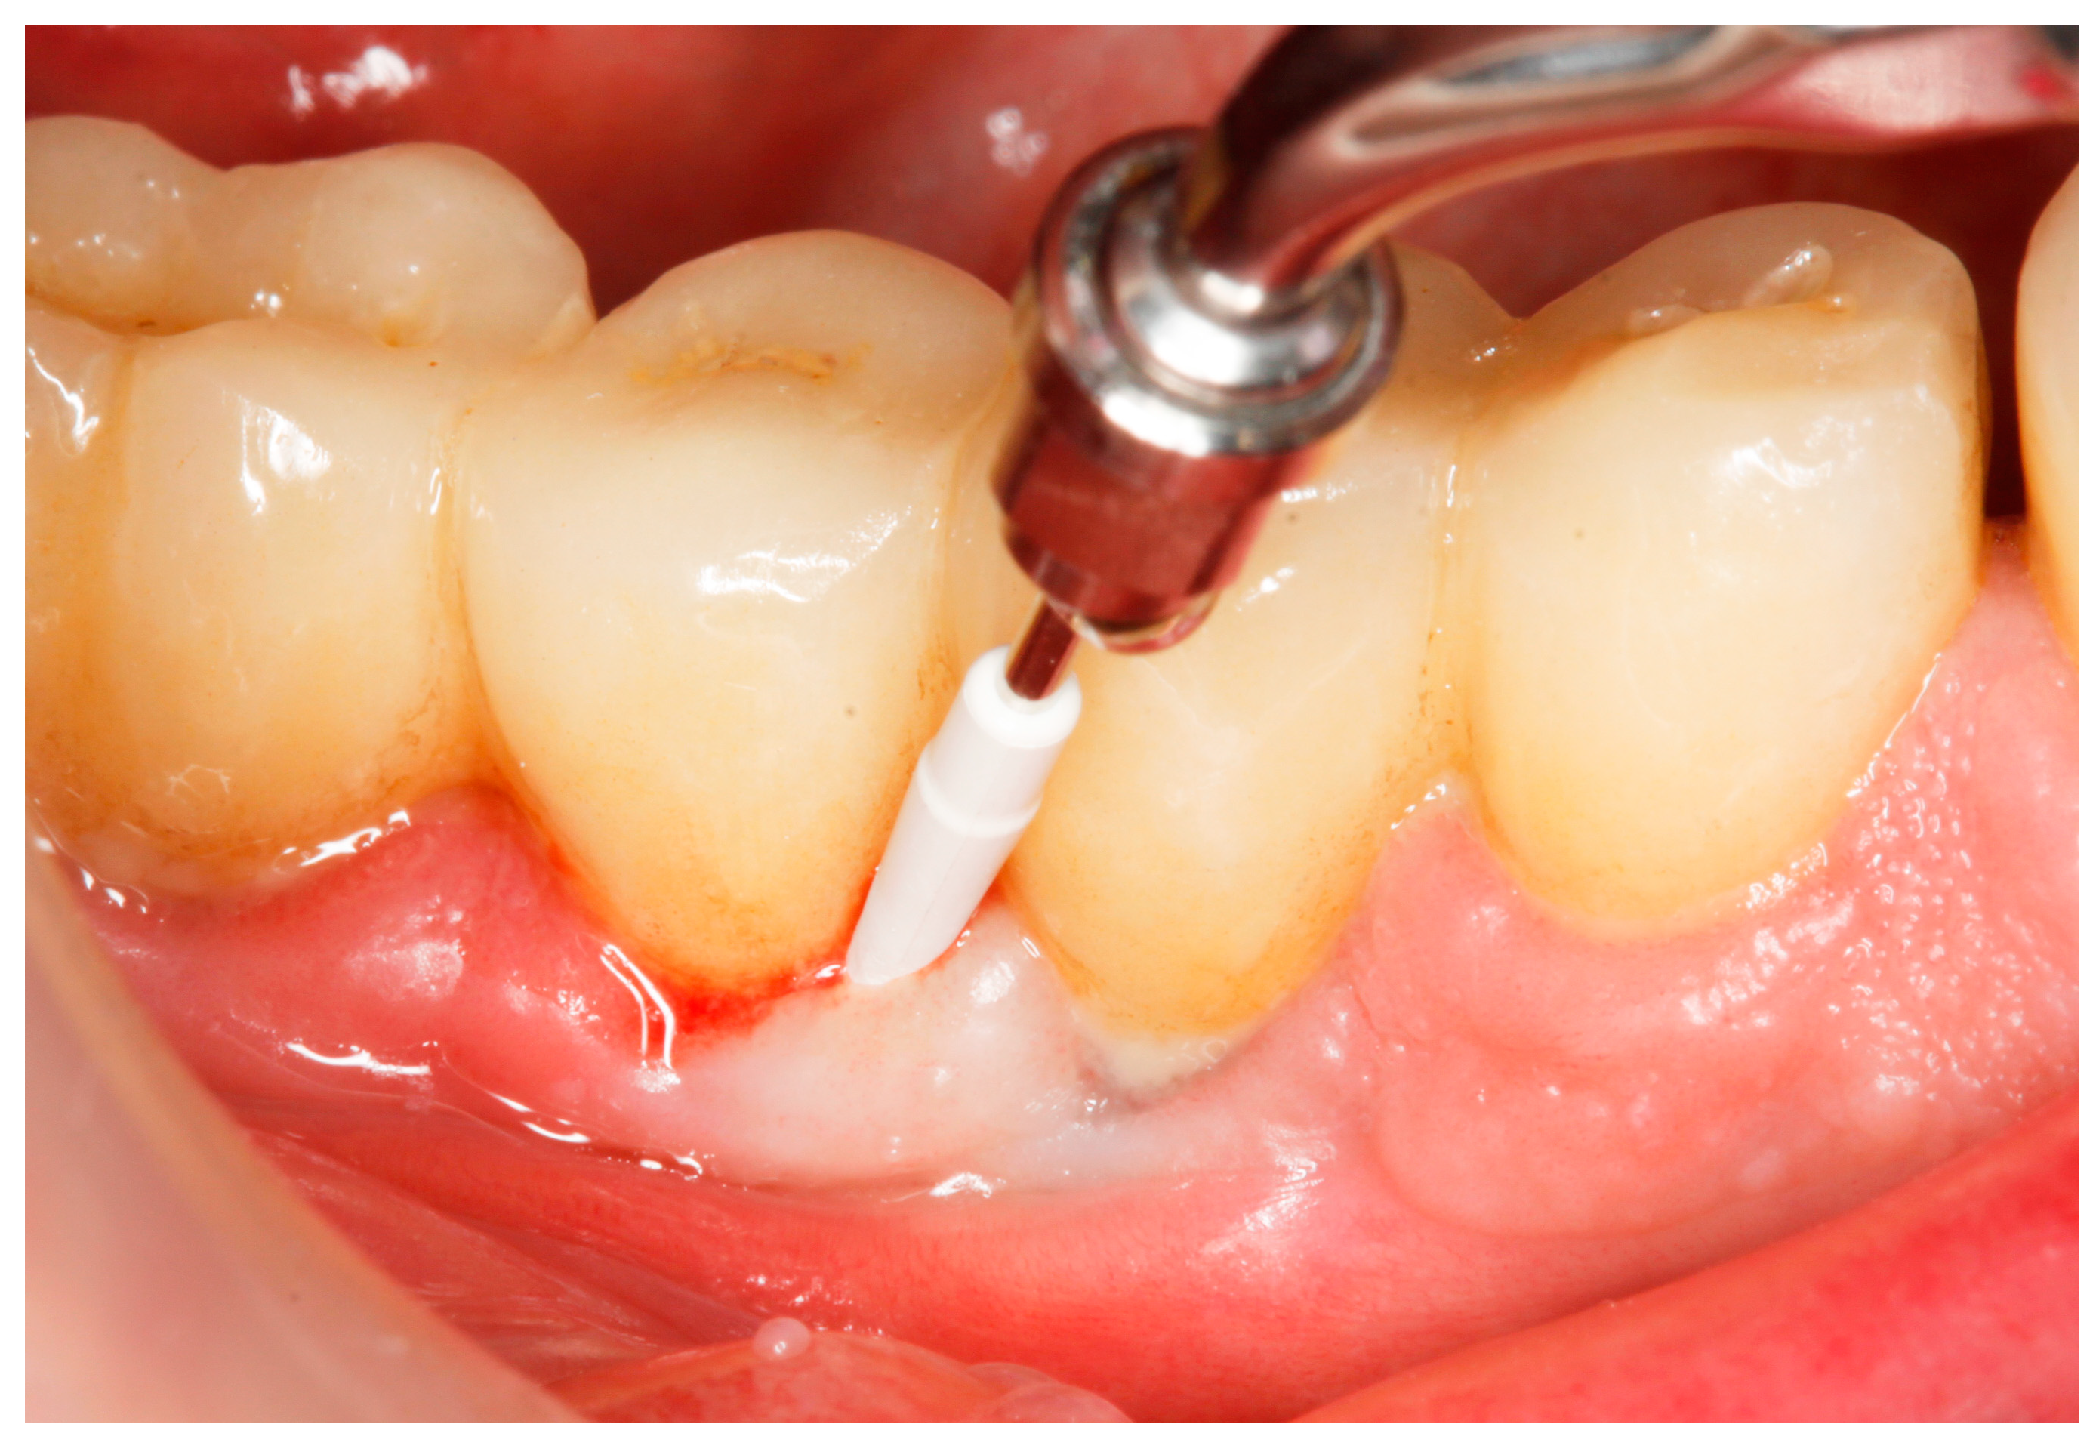

2.8. Treatment Procedures

- PMPR, individualized OH recommendations, for entire dentition/implants;